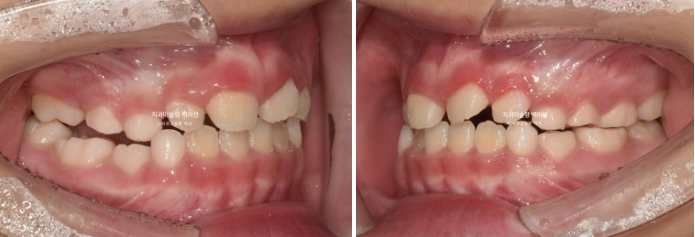

23.05

드디어 앞니 4개가 나왔으며 반대교합 치료 결과는 잘 유지되고 있습니다.

어금니 반대교합의 원인은 좁은 상악 악궁에 있습니다.

이제 인비절라인퍼스트 치료로 악궁확장, 앞니배열 등을 먼저 진행하여 교합간섭 해소를 도모합니다.

23년 6월부터 11월까지, 6개월간 첫세트 30개 장치를 모두 낀 후 모습입니다.

악궁확장을 통해 어금니 반대교합은 해소되었고 앞니배열은 좋아졌습니다.

나중에 영구치 송곳니 날 공간도 충분히 마련되었습니다.